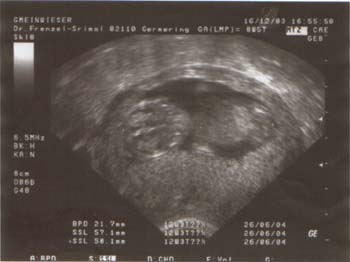

Ihr werdet es kaum glauben, aber Fabian wird bald “großer Bruder”!

Hier gleich das erste Foto:

Diesmal waren wir schneller und haben es schon in der 13. Schwangerschaftswoche erfahren. Die Schwangerschaft verläuft auch anders wie bei Fabian. Anja ist es häufig übel, hat wenig Appetit und Kreuz- und Bauchschmerzen. Wir sind uns deshalb ziemlich sicher, dass es ein MÄDCHEN wird.

Termin ist übrigens am 26.06.2004.